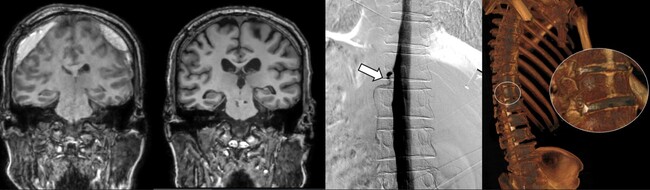

뇌척수액 누출로 위축된 뇌(맨 왼쪽), DSM으로 확인한 누공 위치(세번째), 측위 CT 척수조영술로 확인한 뇌척수액 정맥누공 3D 영상(오른쪽)

세브란스병원은 최근 디지털감산척수조영술(Digital Subtraction Myelography, DSM)을 국내 최초로 도입해 이와 같은 기존 진단법의 한계를 극복했다. DSM은 척수에 조영제를 주입하고 모니터 화면으로 뇌척수액의 흐름을 실시간으로 확인할 수 있다. 이를 통해 뇌척수액이 새나가는 구멍을 정확하게 찾아낼 수 있게 됐다.

DSM과 더불어 세브란스병원이 함께 진행 중인 측위 컴퓨터단층촬영(CT) 척수조영술까지, 모두 뇌척수액 정맥 누공을 진단할 수 있는 최신 기법이다.